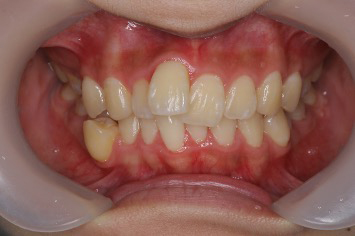

■症例2

Before

After